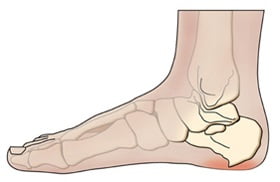

Пяточная шпора — так в народе называют воспалительно-дегенеративный процесс в мягких тканях, окружающих пяточный бугор. Сама по себе пяточная шпора не является отдельным заболеванием, это синдром, который возникает при некоторых патологических состояниях. Его суть заключается в разрастании костной ткани пяточной кости.

Нарост имеет четко определенную локализацию — плантарная поверхность пяточной кости, в области прикрепления длинной связки стопы. Размеры нароста могут колебаться в незначительных пределах, а форма напоминает шпору.

Почему развивается пяточная шпора, и что это такое? Образование шпоры на пяточной кости начинается с возникновения плантарного фасциита. Сначала воспаляется фасция — соединительная ткань подошвы, которая расположена около пяточного бугорка и доходит до пальцев стопы. Затем, если процесс затягивается, происходит кальциноз — пропитка воспаленного участка солями кальция. Так образуется остеофит, который из-за своего характерного вида получил в народе название «шпора».

Пяточная шпора: фото

Как выглядит пяточная шпора, предлагаем к просмотру подробные фото.